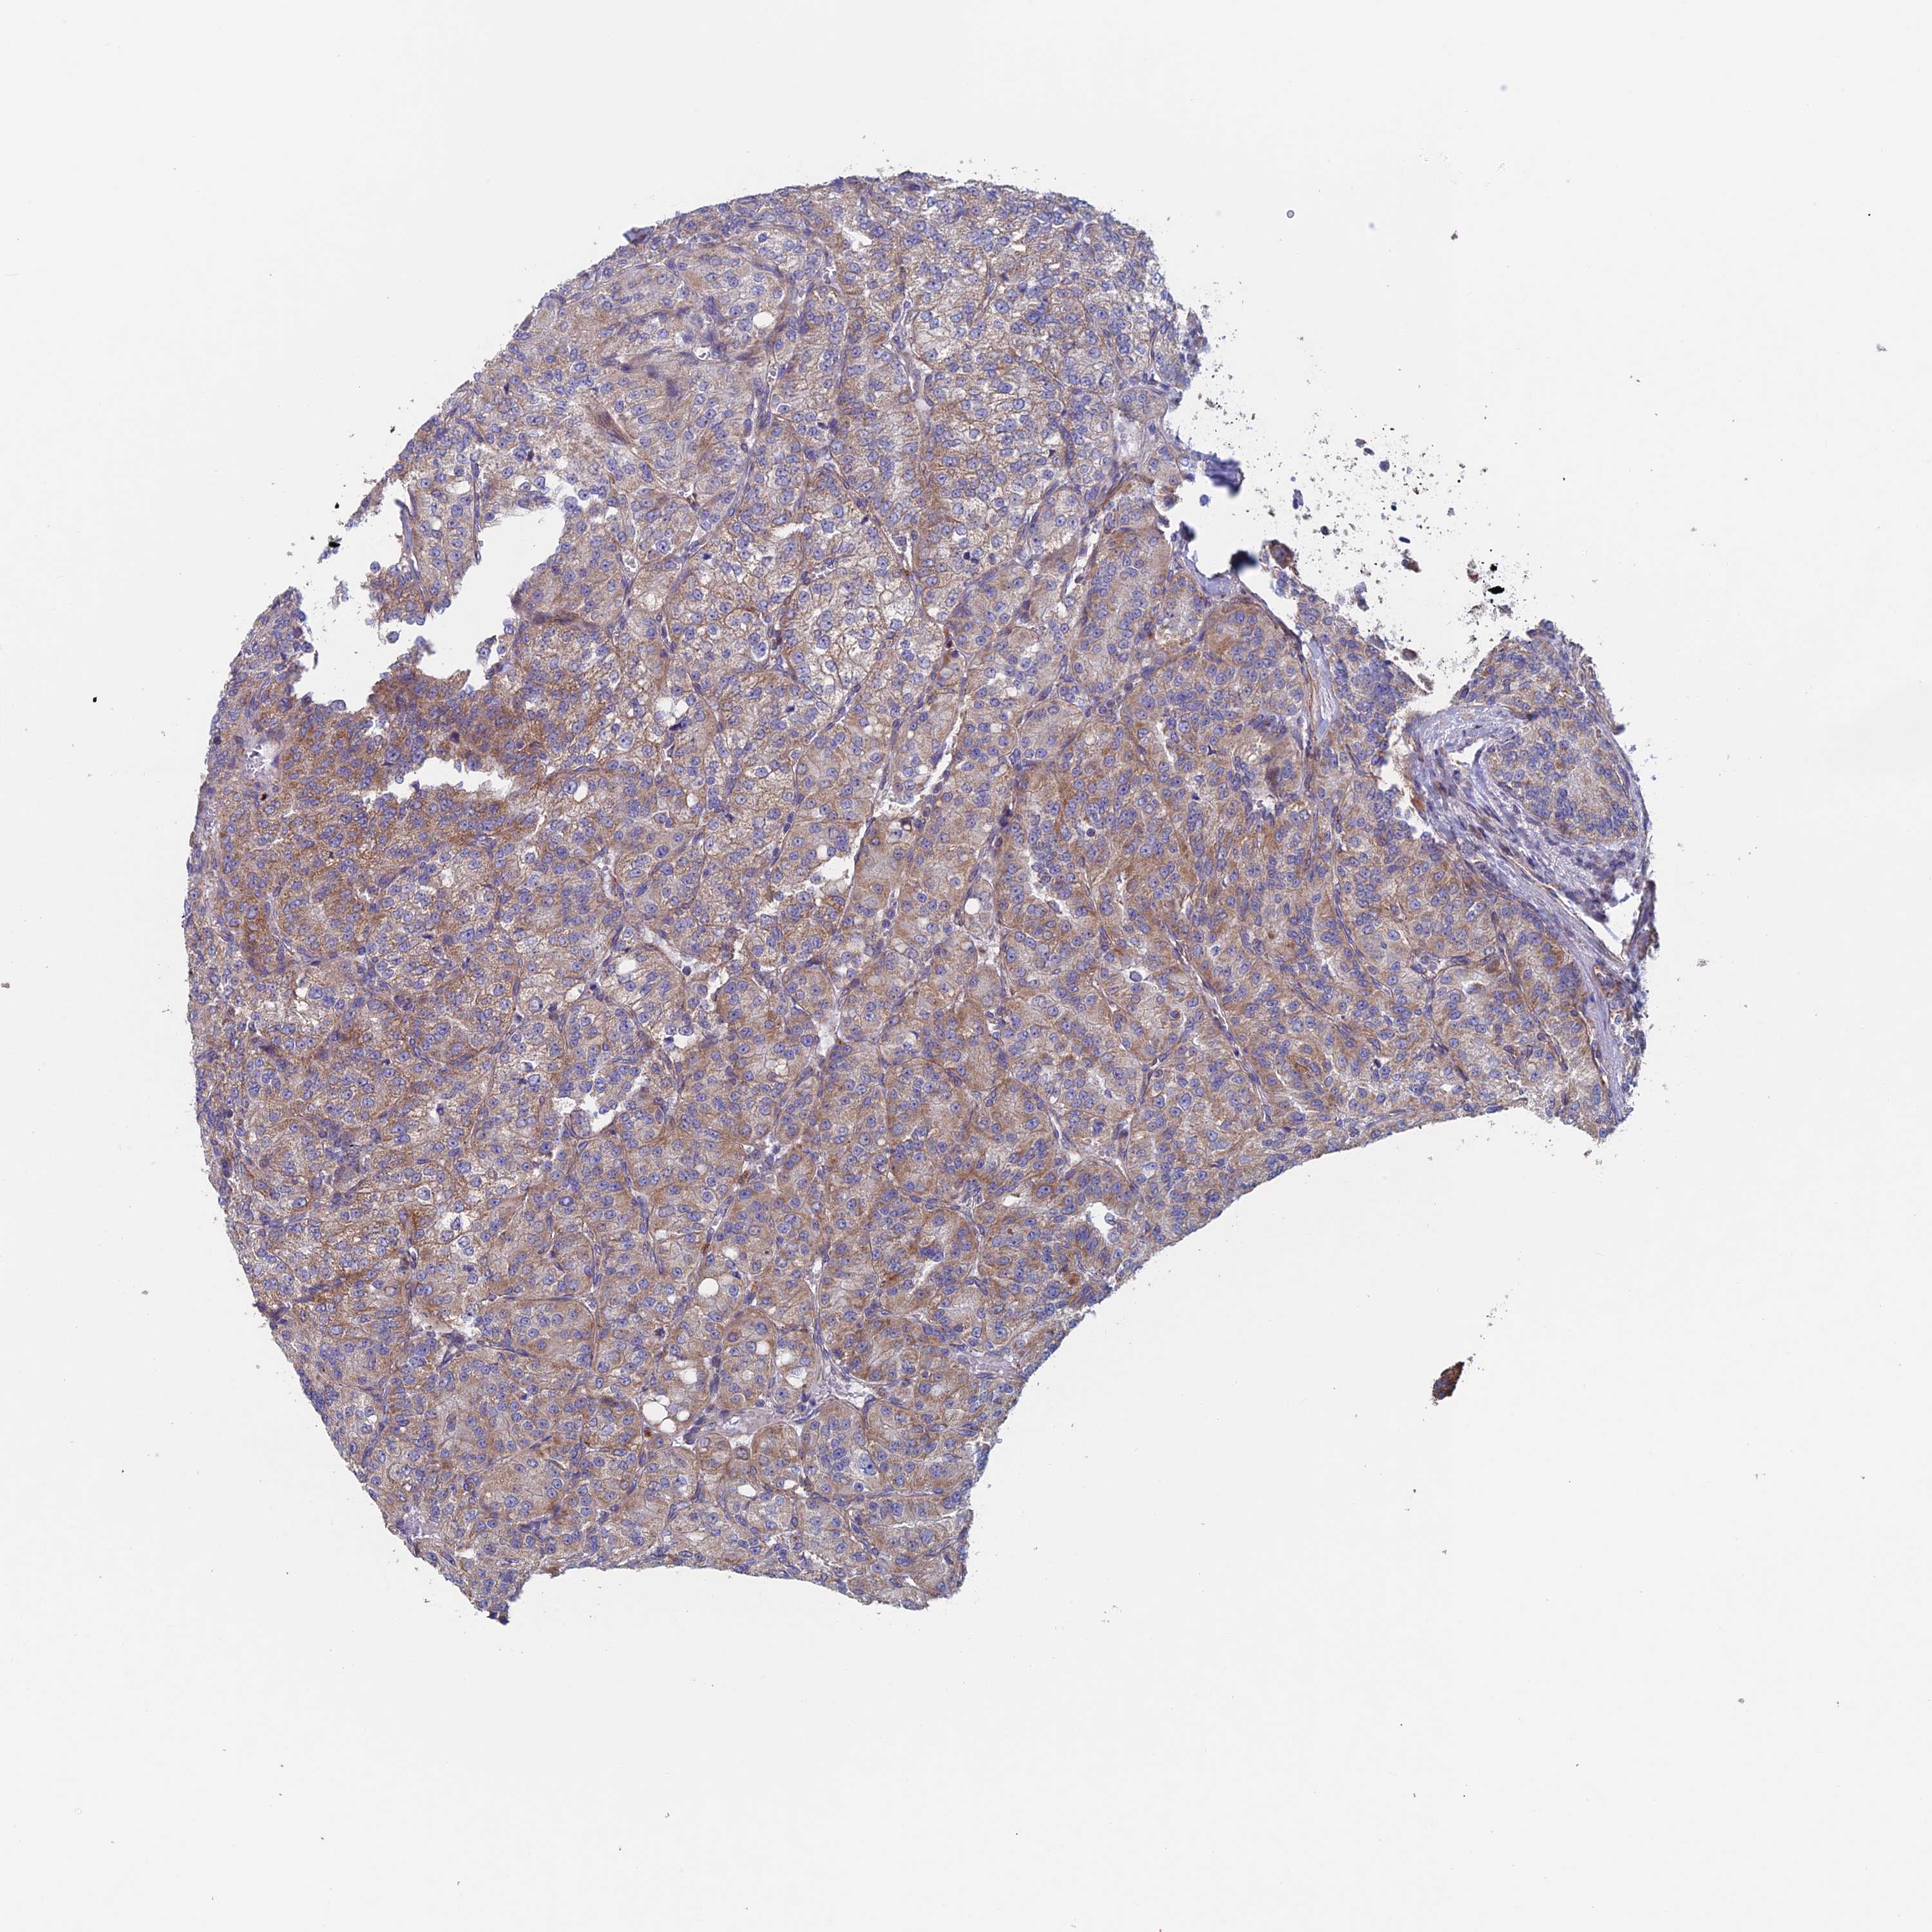

KIDNEY RENAL CLEAR CELL CARCINOMA (TCGA) - Interactive survival scatter ploti

The Survival Scatter plot shows the clinical status (i.e. dead or alive) for all individuals in the patient cohort, based on the same data that underlies the corresponding Kaplan-Meier plots. Patients that are alive at last time for follow-up are shown in blue and patients who have died during the study are shown in red.

The x-axis shows the expression levels (FPKM) of the investigated gene in the tumor tissue at the time of diagnosis. The y-axis shows the follow-up time after diagnosis (years). Both axes are complimented with kernel density curves demonstrating the data density over the axes. The top density plot shows the expression levels (FPKM) distribution among dead (red) and alive patients (blue). The right density plot shows the data density of the survived years of dead patients with high and low expression levels respectively, stratified using the cutoff indicated by the vertical dashed line through the Survival Scatter plot. This cutoff is automatically defined based on the FPKM cutoff that minimizes the p-score. The cutoff can be changed by dragging the vertical line or by entering a cutoff value in the square labeled "Current cut-off".

Under the Survival Scatter plot the p-score landscape (black curve; left axis) is shown together with dead median separation (red curve; right axis). Dead median separation is the difference in median mRNA expression between patients who have died with high and low expression, respectively. It is calculated as follows: median FPKM expression of dead patients with high expression - median FPKM expression of dead patients with low expression. This is intended to aid the user in visually exploring custom cutoffs and the associated p-scores and dead median separation.

Individual patient data is displayed and can be filtered by clicking on one or more of the category buttons on the top of the page. Categories describing expression level and patient information include: high, low, alive, dead, female, male and tumor stages. The scale of the x-axis can be toggled between linear and log-scale by clicking on the "x log" button. Mouse-over function shows TCGA ID, patient information and mRNA expression (FPKM) for each patient.

& Survival analysisi

Kaplan-Meier plots summarize results from analysis of correlation between mRNA expression level and patient survival. Patients were divided based on level of expression into one of the two groups "low" (under cut off) or "high" (over cut off). X-axis shows time for survival (years) and y-axis shows the probability of survival, where 1.0 corresponds to 100 percent.

MRPL1 is potential prognostic, high expression is favorable in Kidney Renal Clear Cell Carcinoma (TCGA)

Best expression cut offi

Based on the FPKM value of each gene, patients were classified into two groups and association between prognosis (survival) and gene expression (FPKM) was examined. The best expression cut-off refers the FPKM value that yields maximal difference with regard to survival between the two groups at the lowest log-rank P-value. Best expression cut-off was selected based on survival analysis .

When clicking on this number, the vertical dashed line indicating cut-off, the interactive survival plot, and the Kaplan-Meier curve will be adjusted to show results based on the best expression cut-off.

: 23.2

TCGA RNA samplesi

RNA-seq data is reported as average FPKM (number Fragments Per Kilobase of exon per Million reads), generated by the The Cancer Genome Atlas (TCGA) .

Normal distribution across the dataset is visualized with box plots, shown as median and 25th and 75th percentiles. Points are displayed as outliers if they are above or below 1.5 times the interquartile range. FPKM values of the individual samples are presented next to the box plot.

Average pTPM 24.2

Number of samples 521